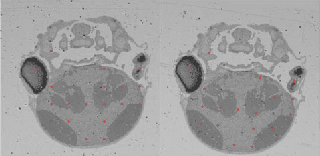

Abstract:In this paper, we propose a novel non-iterative algorithm to simultaneously estimate optimal rigid transformation for serial section images, which is a key component in volume reconstruction of serial sections of biological tissue. In order to avoid error accumulation and propagation caused by current algorithms, we add extra condition that the position of the first and the last section images should remain unchanged. This constrained simultaneous registration problem has not been solved before. Our algorithm method is non-iterative, it can simultaneously compute rigid transformation for a large number of serial section images in a short time. We prove that our algorithm gets optimal solution under ideal condition. And we test our algorithm with synthetic data and real data to verify our algorithm's effectiveness.